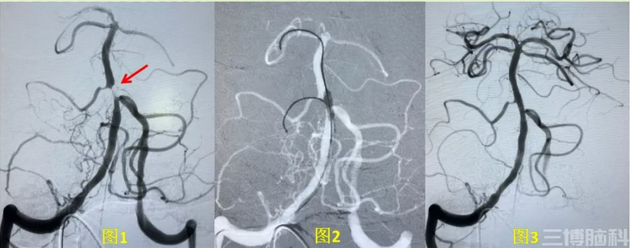

影像资料显示,老吴的的基底动脉高度狭窄达98%(图1),正是由于这段血管闭塞导致患者脑部供血不足,引起肢体麻木、无力,头晕、眼花。病情再发展下去,患者就极可能发生脑梗,情况危急。

刘加春带领团队进行仔细讨论和评估,根据患者病情,确定了基底动脉支架置入血管成形术的手术方案。经过充分的准备工作,包括术前用药、球囊及支架的选择、压力的大小、麻醉方式、术中可能出现的各种并发症及意外情况的应对措施、术后的监护和管理等。11月中旬,刘加春主任应用微导丝实施侧支保护,然后用球囊对狭窄慢慢加压预扩,再置入支架(图2);造影显示狭窄解除,远端供血良好,基底动脉完全开通,手术获得圆满成功(图3)。在介入科医护人员的精心治疗及照料下,老吴术后感觉头脑清晰、双眼明亮、浑身轻松,整个人像年轻了10岁!